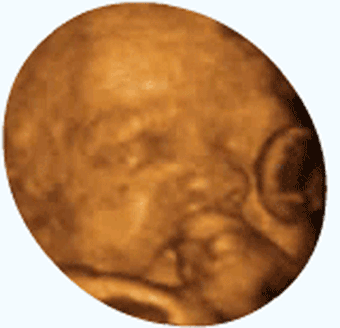

怀孕之后孕妈妈对胎儿的一举一动都是相当关心啊 , 经常会问出意想不到的问题 , 恨不能放个录像机在肚子里了 。 6个月时都可以去做四维彩超了 , 这时胎儿的样子已经接近出生时的模样 , 所以孕妈妈才关心6个月的动静问题吧 。

6个月的胎儿从外观上看已经各就各位、形状完整 , 各项器官也发育完善 , 在肚子里的活动也游刃有余了 。 你知道吗?胎儿除了胎动外 , 还有很多更有意思的事情 , 一起来看看吧 。

会做鬼脸

胎儿特别会做鬼脸 , 挤眉弄眼 , 玩得可欢了 。 最四维彩超的时候可以仔细观察一下胎儿的动作 , 还是蛮有意思的 。